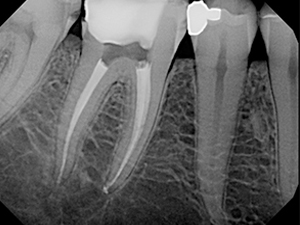

Images of case of RCT

Case : Single Sitting Protaper Molar Rct

After Treatment